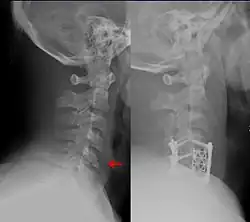

A fracture of the lower cervical vertebrae, one of the conditions treated by orthopedic surgeons and neurosurgeons